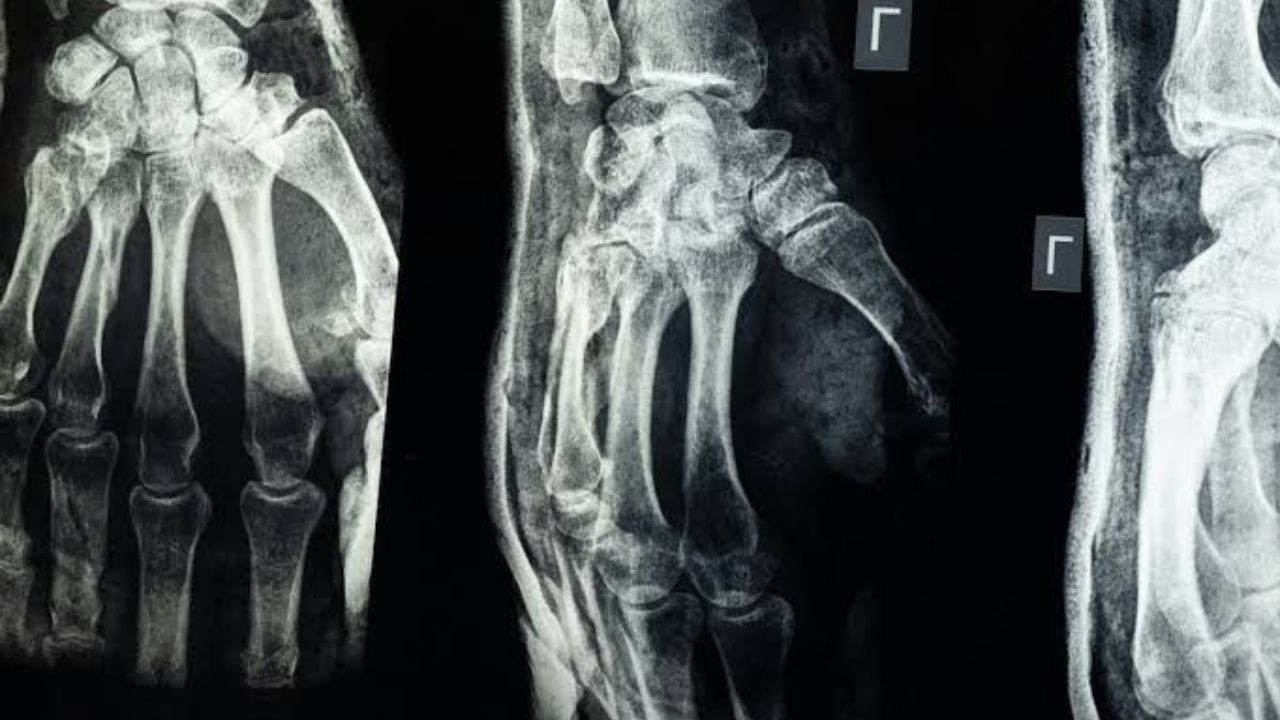

Bone Glue: चिकित्सा विज्ञान में एक ऐसी क्रांति आ रही है जो हड्डी टूटने के इलाज को पूरी तरह बदल सकती है. पूर्वी चीन के झेजियांग प्रांत के शोधकर्ताओं ने 'बोन-02' नामक एक अभूतपूर्व हड्डी चिपकने वाली पदार्थ विकसित किया है, जो फ्रैक्चर और चूर-चूर हो चुकी हड्डियों को मात्र तीन मिनट में जोड़ सकता है.

लिन जियानफेंग के अनुसार, यह चिपकने वाला पदार्थ रक्त से भरपूर वातावरण में भी दो से तीन मिनट के अंदर सटीक स्थिरिता हासिल कर लेता है. सबसे खास बात यह है कि हड्डी ठीक होने पर यह पदार्थ शरीर द्वारा स्वाभाविक रूप से अवशोषित हो जाता है, जिससे प्रत्यारोपण हटाने के लिए दूसरी सर्जरी की जरूरत नहीं पड़ती. पारंपरिक तरीकों में बड़े चीरे लगाकर स्टील प्लेट और स्क्रू लगाए जाते हैं, लेकिन यह चिपकने वाली तकनीक न्यूनतम इनवेसिव है. सीसीटीवी के मुताबिक, 'बोन-02' को 150 से अधिक मरीजों पर सफलतापूर्वक परीक्षण किया जा चुका है.

शरीर में रॉड डालने से मिलेगा छुटकारा

प्रयोगशाला परीक्षणों से पुष्टि हुई कि 'बोन-02' सुरक्षा और प्रभावशीलता के मानदंडों पर खरा उतरा. एक परीक्षण में प्रक्रिया 180 सेकंड से कम समय में पूरी हो गई. चिपकाई गई हड्डियों ने 400 पाउंड से अधिक अधिकतम बंधन बल, लगभग 0.5 एमपीए की शीयर स्ट्रेंथ और करीब 10 एमपीए की संपीड़न स्ट्रेंथ दिखाई, जो पारंपरिक धातु प्रत्यारोपण को बदलने की क्षमता दर्शाता है. वैज्ञानिकों का कहना है कि इससे विदेशी पदार्थ प्रतिक्रिया और संक्रमण के जोखिम कम हो जाते हैं. वर्तमान बाजार में हड्डी सीमेंट और खालीपन भरने वाले पदार्थ उपलब्ध हैं, लेकिन इनमें चिपकने की कोई क्षमता नहीं है.